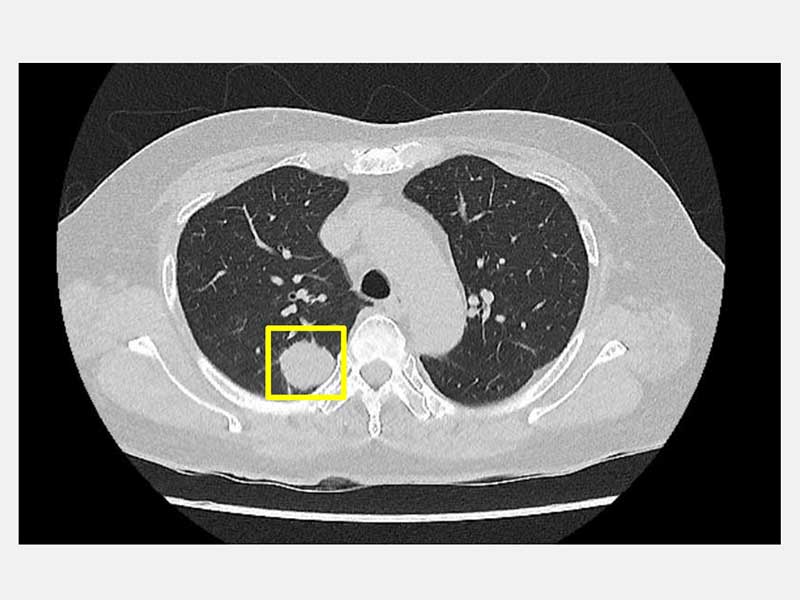

50歲的吳先生平時生活作息規律,從不抽菸,也沒有肺癌家族史,原以為自己身體健康的他在一次健康檢查中,經由低劑量電腦斷層(LDCT)意外發現右側肺部有一顆約2公分大小的腫瘤。吳先生前往仁愛長庚合作聯盟醫院尋求醫療專業協助,經由胸腔暨心臟血管外科林宜右醫師詳細評估後,建議進行肺臟腫瘤切除手術,並且採用目前先進的「單孔達文西機器人微創手術」技術,在三天內順利出院。